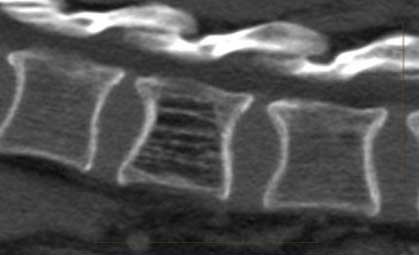

Гемангиома в грудном отделе (а). Опухоль имеет сосудистое происхождение и сливается с паравертебральными сосудами (с,d)